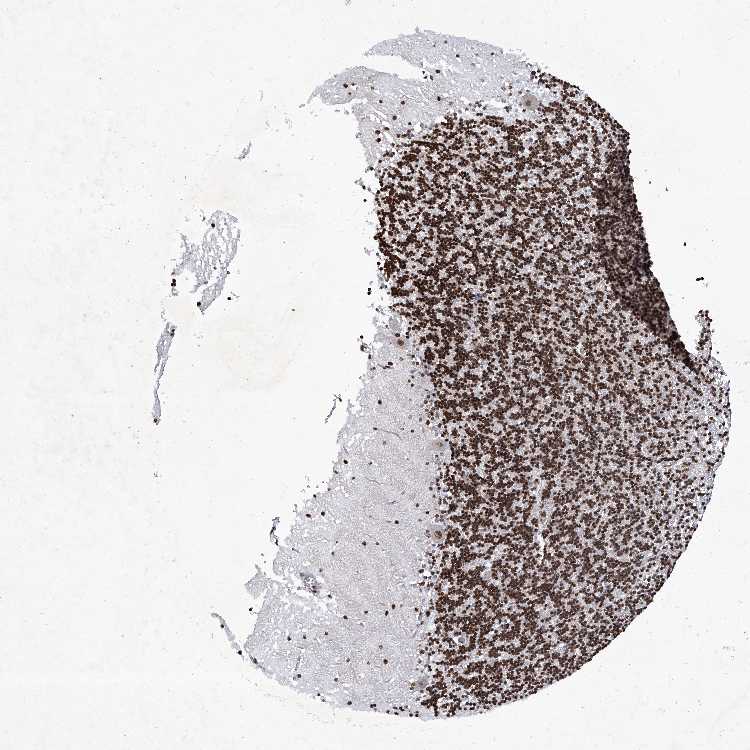

CEREBELLUM - Antibody stainingi

Antibody staining in the annotated cell types in the current human tissue is reported as not detected, low, medium, or high, based on conventional immunohistochemistry profiling in selected tissues. This score is based on the combination of the staining intensity and fraction of stained cells.

Each image is clickable and will lead to virtual microscopy that enables deeper exploration of all samples and also displays staining intensity scores, fraction scores and subcellular localization as well as patient and tissue information for each sample.

Antibody CAB032824

Purkinje cells Medium

Cells in granular layer High

Cells in molecular layer High